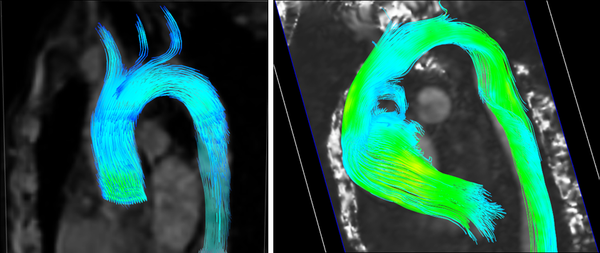

Other importance feature in many cardiovascular diseases is the helical flow patterns and turbulent blood flow, characterized by fast random temporal and spatial velocities fluctuations[25]. These irregular and rapid fluctuations are not present in healthy situations, and play also a key role in some cardiovascular pathologies. The helical flow patterns show a measure(index) of blood flow complexity, and therefore, is an important factor in the development of cardiovascular disease, as shown in figure 4. Given the fluid flow velocity vector field u, the vorticity vector field w is the curl of the velocity field:

|

| Figure 4: Left: Streamlines in a healthy aorta. Right: Streamlines in unhealthy aorta |